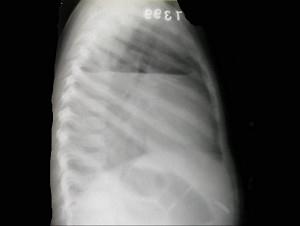

男,7岁,外伤后突发呼吸困难伴胸痛,结合图像,最可能的诊断是?(?)A.胸腔积液B.肺大泡C.气胸D.液气胸E.肺脓肿

问题 男,7岁,外伤后突发呼吸困难伴胸痛,结合图像,最可能的诊断是?(?)

选项 A.胸腔积液 B.肺大泡 C.气胸 D.液气胸 E.肺脓肿

答案 D